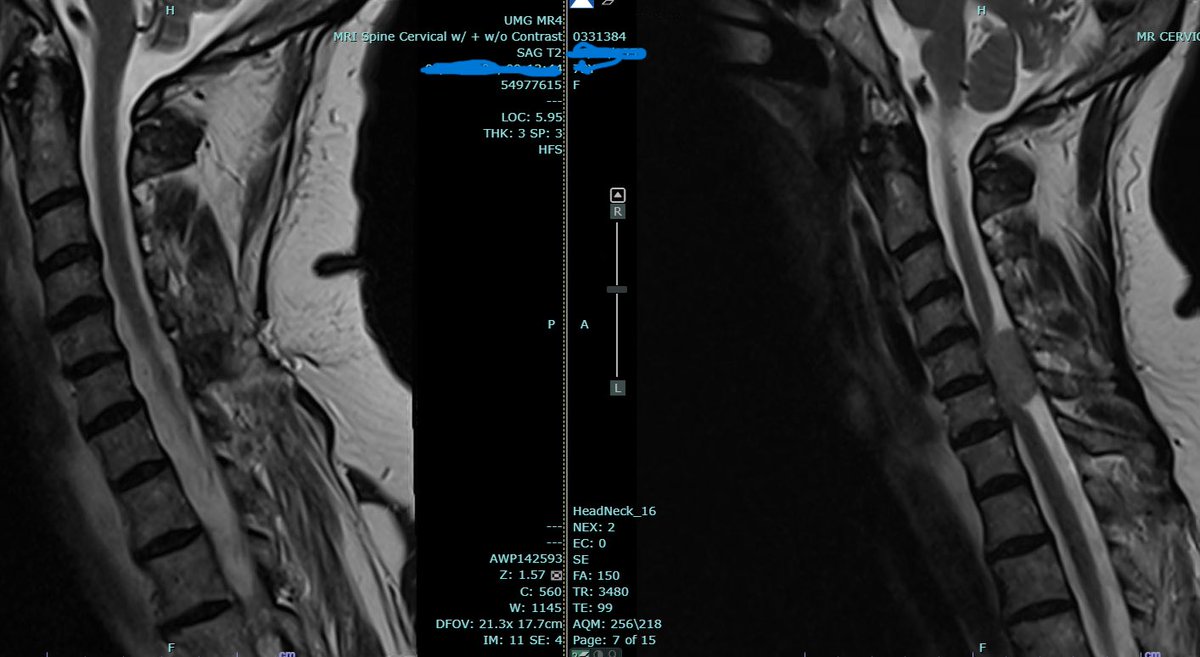

Incredibly grateful for the privilege of being a #neurosurgeon and helping make an impact on my patient’s lives…Especially this week when I’ve seen some recent patients who trusted me to do their #brainsurgery or #spinesurgery.